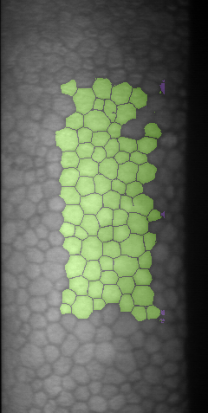

Specular microscopy assessment of the human corneal endothelium (CE) in Fuchs' dystrophy is challenging due to the presence of dark image regions called guttae. This paper proposes a UNet-based segmentation approach that requires minimal post-processing and achieves reliable CE morphometric assessment and guttae identification across all degrees of Fuchs' dystrophy. We cast the segmentation problem as a regression task of the cell and gutta signed distance maps instead of a pixel-level classification task as typically done with UNets. Compared to the conventional UNet classification approach, the distance-map regression approach converges faster in clinically relevant parameters. It also produces morphometric parameters that agree with the manually-segmented ground-truth data, namely the average cell density difference of -41.9 cells/mm2 (95% confidence interval (CI) [-306.2, 222.5]) and the average difference of mean cell area of 14.8 um2 (95% CI [-41.9, 71.5]). These results suggest a promising alternative for CE assessment.